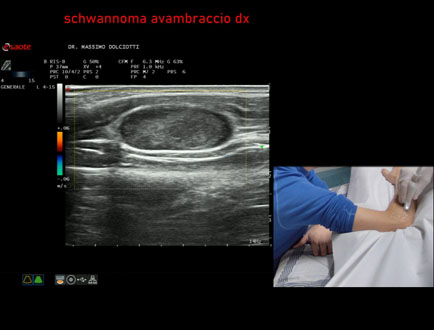

Età Paziente: M 48 anni

Motivazione dell'esame: da circa 1 anno rilievo di tumefazione all'avambraccio destro.

Commento all'esame: le immagini ed il video documentano, all'avambraccio destro, all'interno del muscolo estensore delle dita, formazione ipoecogena a margini definiti, delle dimensioni di 28,5 mm per uno spessore di 12,1 mm, con modesti segni di vascolarizzazione intra nodulare, da ricondurre, come prima ipotesi, a Schwannoma.

Conclusioni: schwannoma all'avambraccio destro (schwannoma of the right forearm).